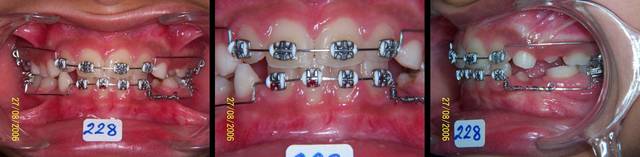

Voici un cas qui ressemble un peu a ton cas, en moins grave, mais qui peut te donner une idee sur ce qu'il faut faire.

Bref, le systeme de MacAndrews peut etre utile dans ces cas. Un arc de base de stabilisation basic, jambe du cote de la deviation contre la laterale, le cote oppose est a distance pour permettre le mouvement des 4 incisives. Une boucle au milieu du pont lateral sert de stop pour le ressort active de la quantite de deplacement desiree avec 3 mm de plus et insere pendant la fabrication de l'arc de base. On laisse faire le systeme tout seul.

Abd - Eugenol

Abd ressort cyjkzt - Eugenol

Abd ressort 2 mg2ndd - Eugenol

Abd fin lv84yz - Eugenol